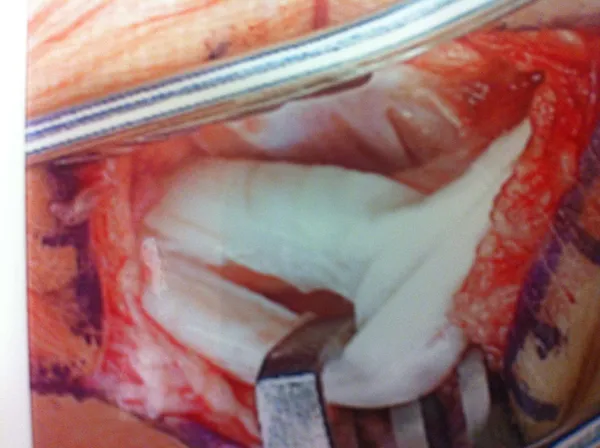

Final Placement of Peroneal Tendons back in the fibular groove and suture replacement for repair of Superior Peroneal Retinaculum and Tendon Sheath. (below)